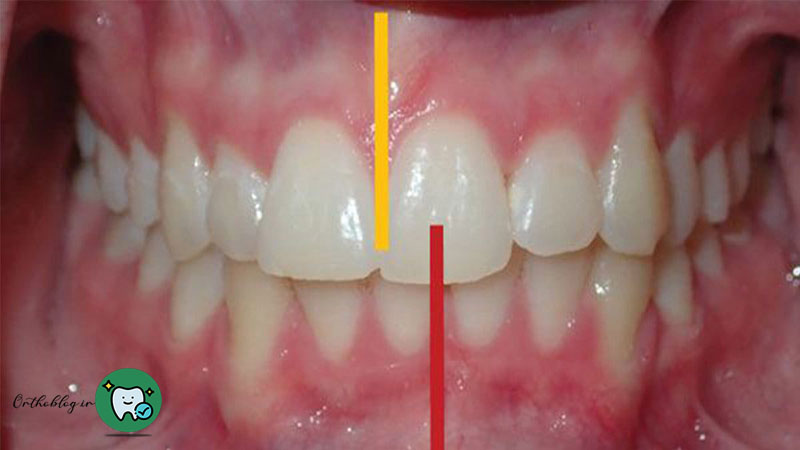

همچنین اگر بین دندان ها بیش از حد فاصله افتاده باشد یا دندان ها از خط وسط تراز نباشد ممکن است به درمان پیچیده تری نیاز باشد.

تراز بودن دندان ها از خط وسط

یکی دیگر از مواردی که ارتودنتیست ها به آن توجه دارند، تراز بودن دندان ها در خط وسط است. اگر دندان های شما در فک بالایی و فک پایینی در خط وسط تراز نباشد حتی اگر دندان هایتان مرتب باشد شما به درمان پیچیده تری نیاز دارید.